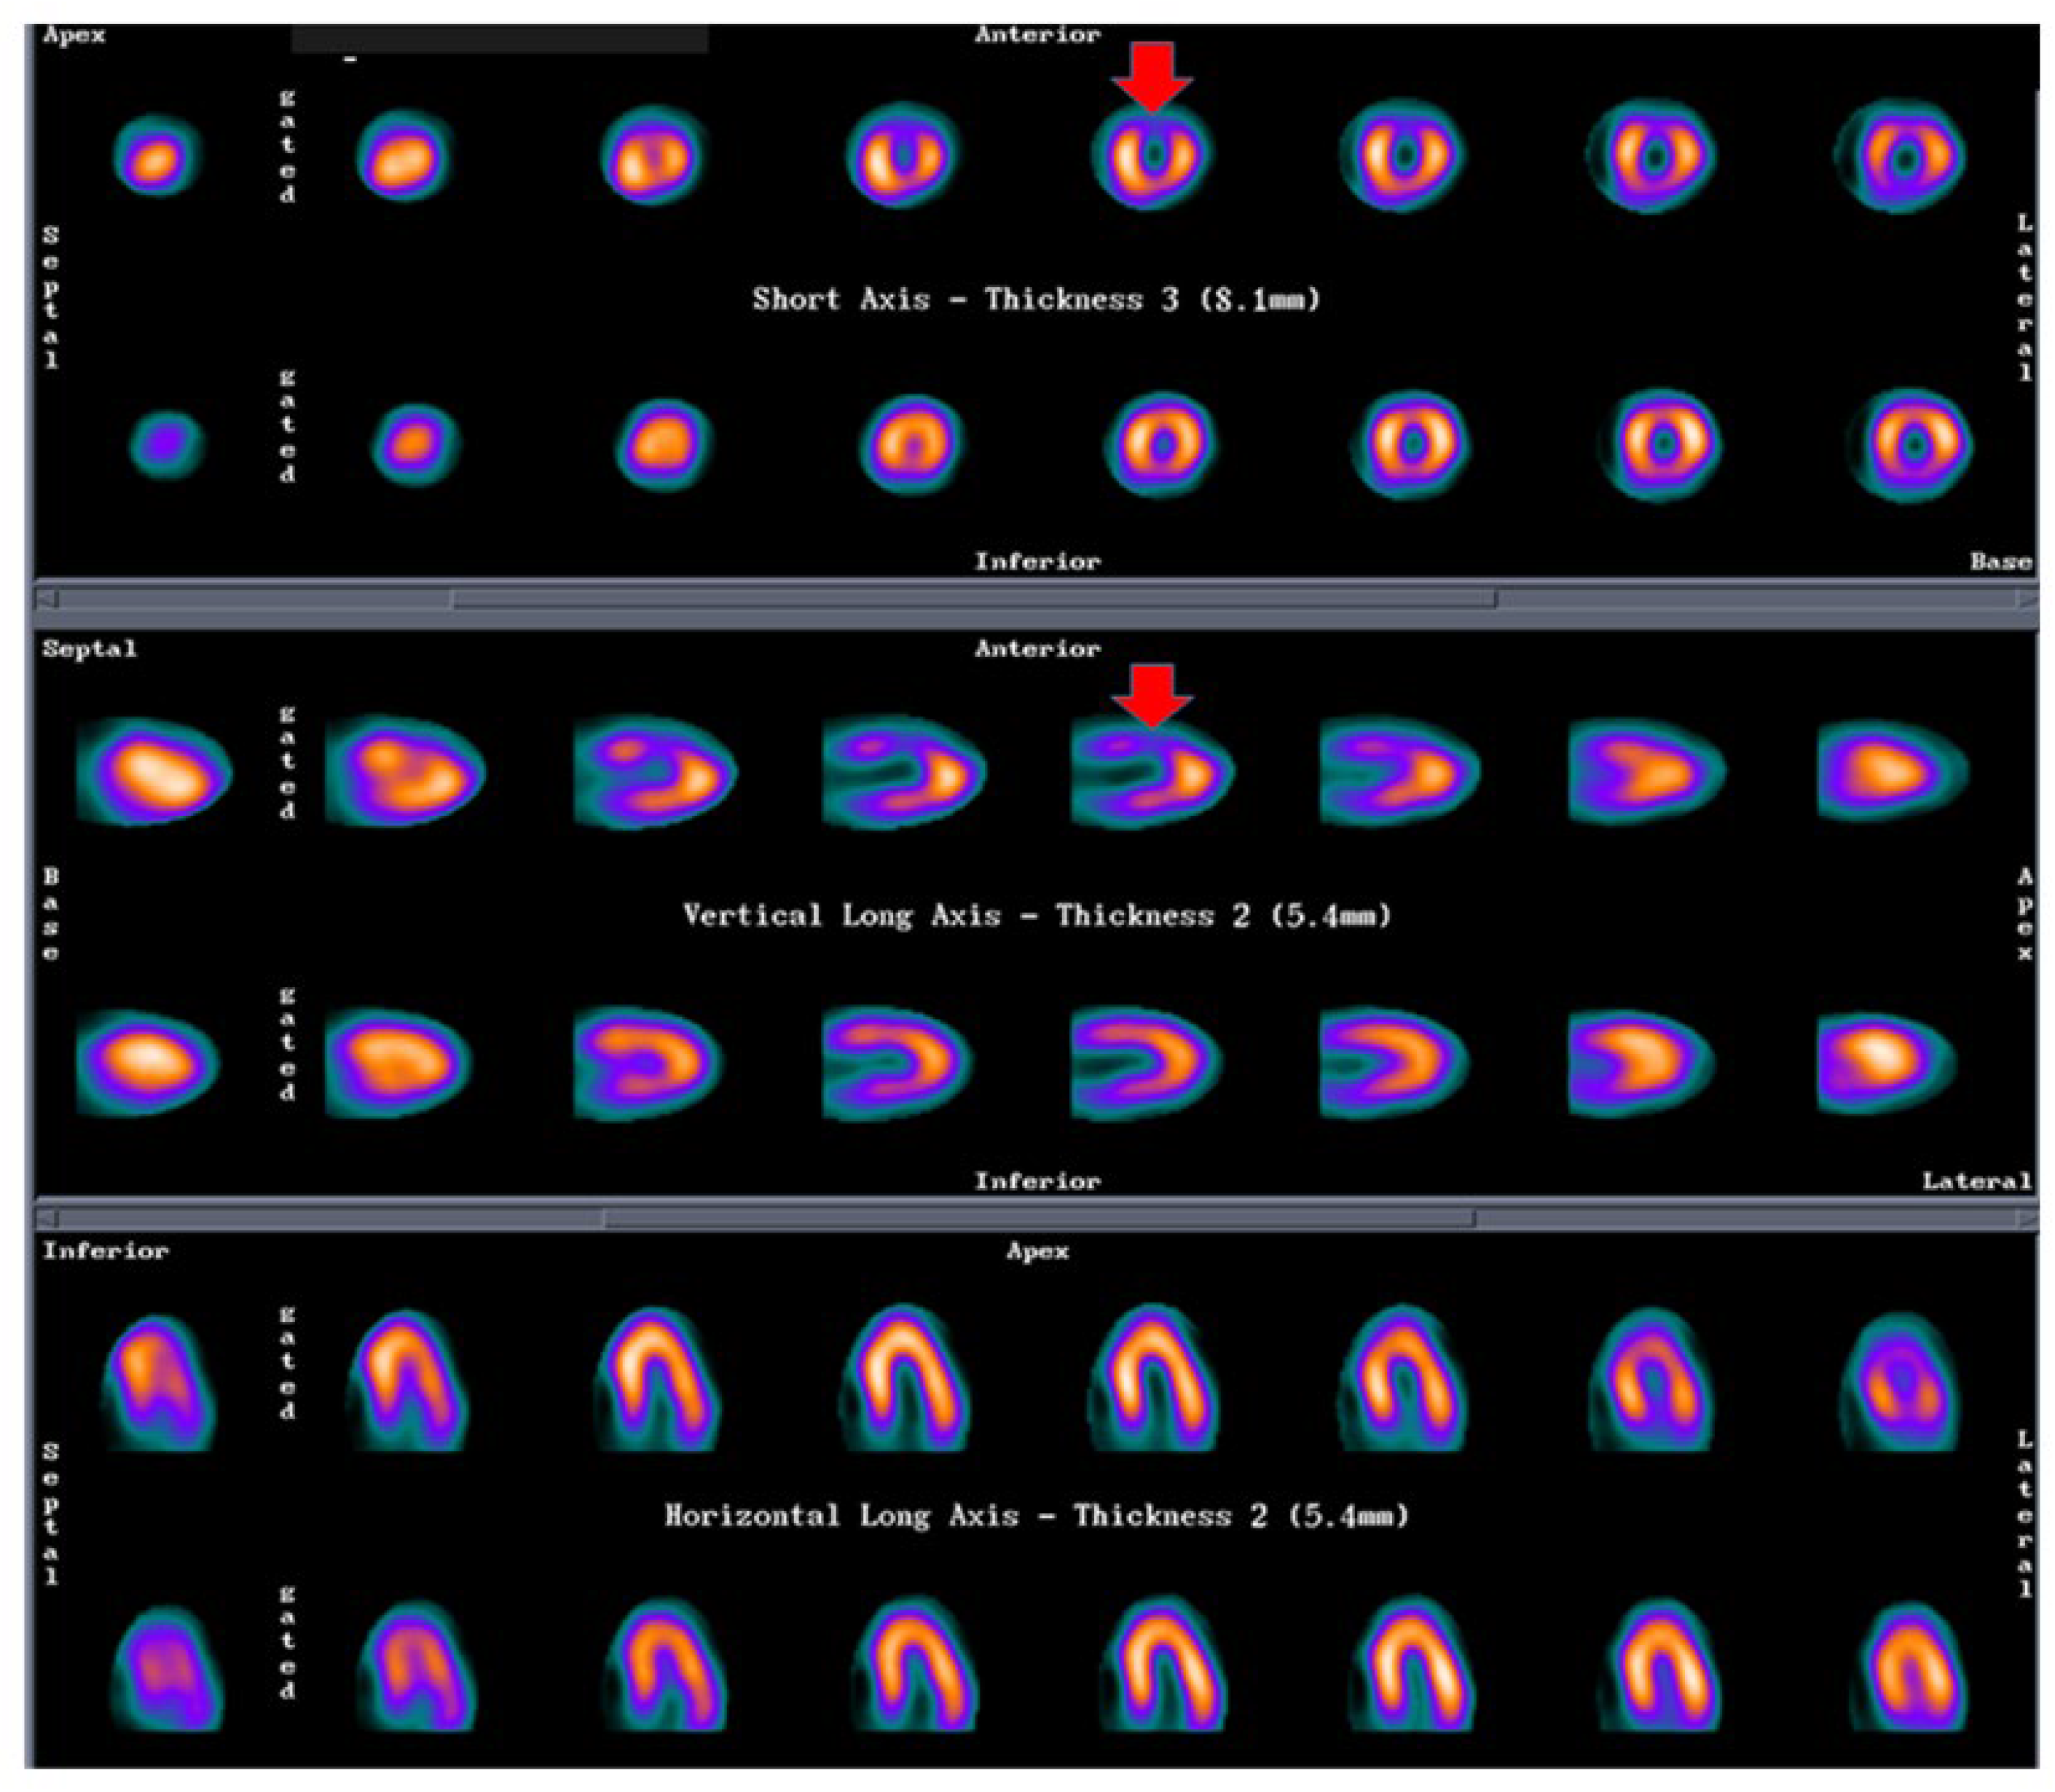

- Although the role of nuclear imaging in TTS has not yet been well established in clinical practice, assessments of myocardial perfusion, adrenergic innervation and metabolic activity may help in the diagnosis [88,89]. For instance, if there is normalized LV wall motion, the delayed recovery of glucose metabolism (by FDG-PET) and sympathetic innervation (by 123I-MIBG scintigraphy) may allow for the diagnosis of TTS in patients with delayed presentation. Although the coronary microcirculation is transiently compromised in TTS, its physiological role is still unclear. A reduction of perfusion tracer counts as a result of regional myocardial wall thinning at the apex, due to both artefacts and partial volume effects, which may mimic ACS, has been reported [86]. Figure 4 (SPECT-MPI) and Figure 5 (CMR) present the case of a patient with TTS.